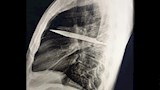

في واقعة طبية نادرة، اكتشف أطباء في تنزانيا شفرة سكين معدنية كبيرة مستقرة داخل تجويف صدر رجل يبلغ من العمر 44 عاما، بعد مرور ثماني سنوات على تعرضه لطعنات متكررة دون أن يعلم ببقاء الشفرة في جسده.

وأظهرت الفحوص السريرية أن الجزء الأيمن من صدره لا يتمدد بالكامل أثناء التنفس، فيما كشفت الأشعة السينية وجود شفرة سكين كبيرة عالقة في تجويف الصدر، ممتدة من الظهر إلى مقدمة القفص الصدري، ومحاطة بطبقات من القيح والأنسجة الميتة.